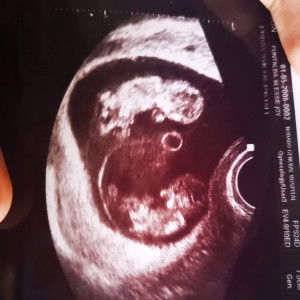

Hello po ask ko lang po sana if ilang weeks weeks tummy niyo nung nag start na magkaron ng milk yung breast niyo? Im turning 32weeks na po kasi wala pading any signs of milk na lumalabas sa breast ko e. First time mom po. Thank you